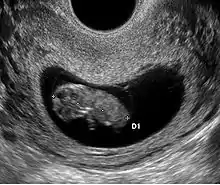

- Le premier signe échographique d'une grossesse est la visualisation d'un sac ovulaire. Il est visible entre 4 semaines et 1 jour et 4 semaines et 3 jours; Il mesure alors 2 à 3 mm. L'utilisation de la voie endovaginale est souvent nécessaire pour le voir. Le sac ovulaire a l'aspect d'une petite tache noire, excentrée par rapport à la cavité utérine, correspondant à la cavité chorionique entourée d'une couronne d'échogénéicité forte : le trophoblaste.

- À cinq semaines, le sac ovulaire mesure 5 mm. Il est quasiment toujours visible lors de l'échographie par voie abdominale. Il est parfois difficile d'affirmer la localisation intra-utérine de la grossesse en raison de l'aspect de pseudo-sac gestationnel décrit au cours des grossesses extra-utérines. Seuls deux signes sont pathognomoniques de la grossesse intra-utérine

- L'aspect en double cercle du sac (double decidual sac sign) correspondant une couronne hyper-échogène interne en rapport avec la trophoblaste et une couronne hypo-échogène externe en rapport avec la transformation gravidique de l'endomètre

- La visualisation de la vésicule vitelline qui affirme définitivement le caractère ovulaire de l'image échographique.